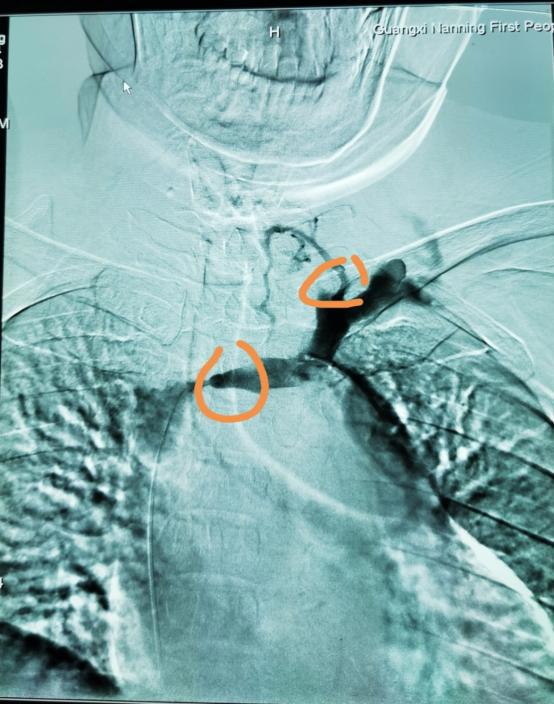

血液透析血管通路的建立与维护:科室拥有血管通路医护团队,设有血管通路专病门诊,多学科协同术前彩色多普勒血管超声检查、术中超声引导以及术后通路超声复查、复杂血管通路及中心静脉的CT血管成像(CTA)和数字减影血管造影(DSA),可开展经皮B超引导下内瘘血管腔内成形术(PTA)、肢体静脉动脉内瘘手术、中心静脉血透导管置入术以及DSA下中心静脉狭窄球囊扩张后建立血透导管等疑难复杂通路的问题。

图 DSA治疗肿胀手综合征